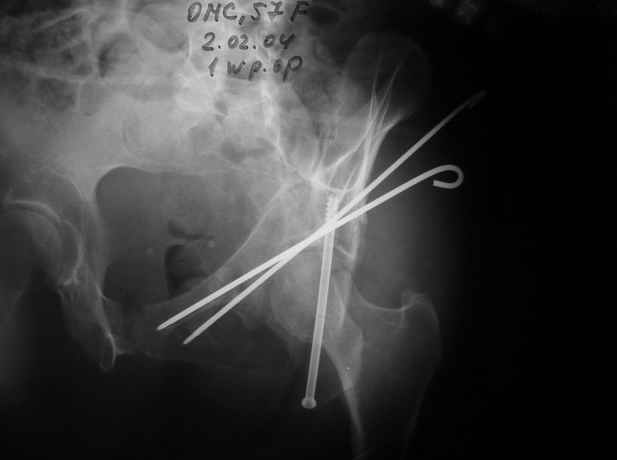

Однако есть альтернатива. Репозиция из подвздошного доступа тазовыми щипцами с разнодлинными браншами или тазовым пистолетом, а фиксация задней колонны через седалищный бугор или тазрвыми винтами 4,5 или каннюлированными 6,5 или 7,3. По-моему я посылал на ортофорум такой снимок, когда жаловался на ишемический неврит седалищного нерва через сутки после операции. Не забудь про шейку бедра - мне кажется будет хорош длинный PFN любой фирмы, какую ты найдешь, а нет так UFN + miss a nail, как это здорово делают мои земляки - Ебурбуки. Пока.

02.02.04